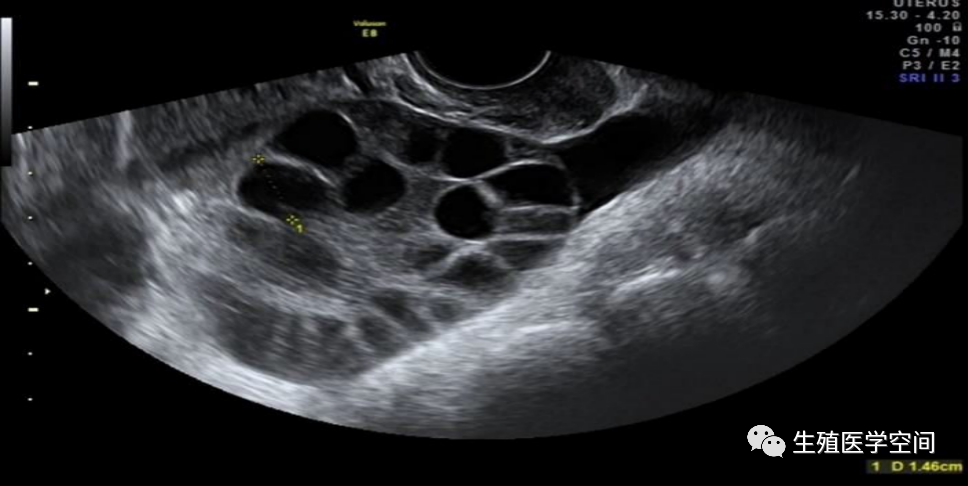

图片

B超检测下的一侧卵巢切面及其内的多个卵泡(卵巢过度刺激)